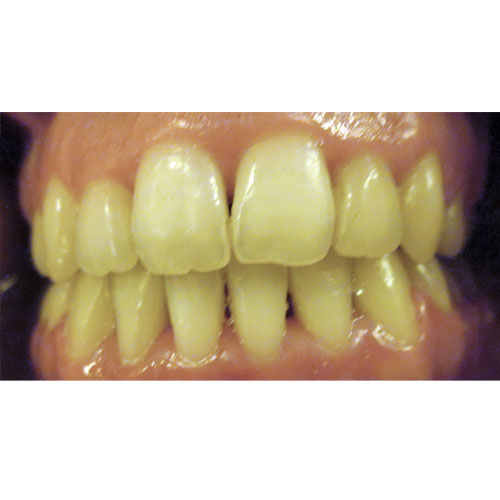

Nasze rezultaty